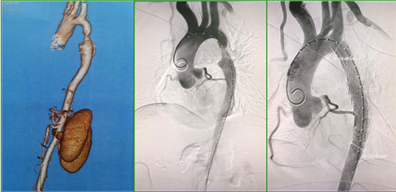

介入治疗(首选):通过导管将“球囊”送到狭窄部位,扩张血管后植入支架,创伤小、恢复快,适合大多数成人患者;